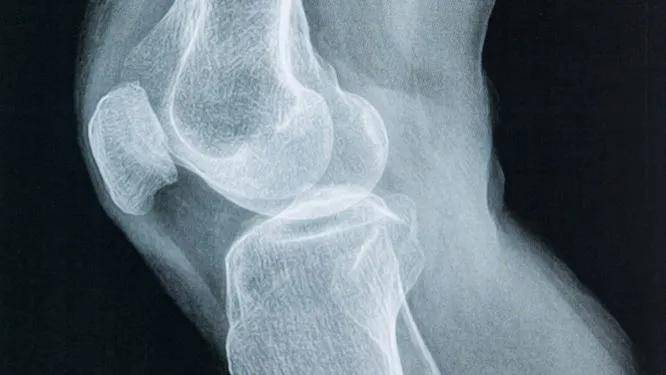

膝盖总是疼痛?祸根或是"滑膜炎"!教你4个方法,积液也拜拜什么是滑膜炎?滑膜炎,顾名思义,是指膝关节滑膜的炎症。滑膜是覆盖在关节表面的薄膜,负责分泌关节液,保持关节的润滑和营养。滑膜炎会导致滑膜增厚、渗出,进而引起膝盖疼痛、肿胀和活动受限。据最新的统计数据显示,滑膜炎在中老年人群中发病率较高,尤其是那些经常进行高强度...

膝盖炎症大揭秘:你不可不知的那些事膝盖是人体重要的关节之一,承担着身体的重量和运动功能。当膝盖出现炎症时,会给我们的生活带来诸多不便。那么,膝盖炎症有哪些呢?下面就为大家详细介绍一下。首先,让我们来认识一下膝盖炎症的类型:1、滑膜炎滑膜炎是指滑膜受到刺激产生炎症,导致分泌液失调形成积液的一种关...